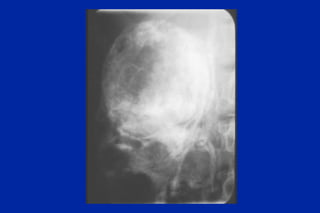

Este documento resume los principales tipos y técnicas de angiografía. Describe brevemente la angiografía, arteriografía, flebografía y linfografía, así como las técnicas de contraste y materiales utilizados. También explica los principales accesos vasculares, la técnica de Seldinger, la angiografía por sustracción digital y algunas técnicas endovasculares comunes.